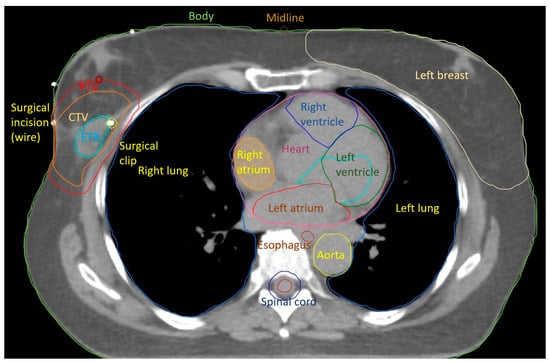

6. Regional Lymph Node Irradiation and Risk of Serious Toxicity